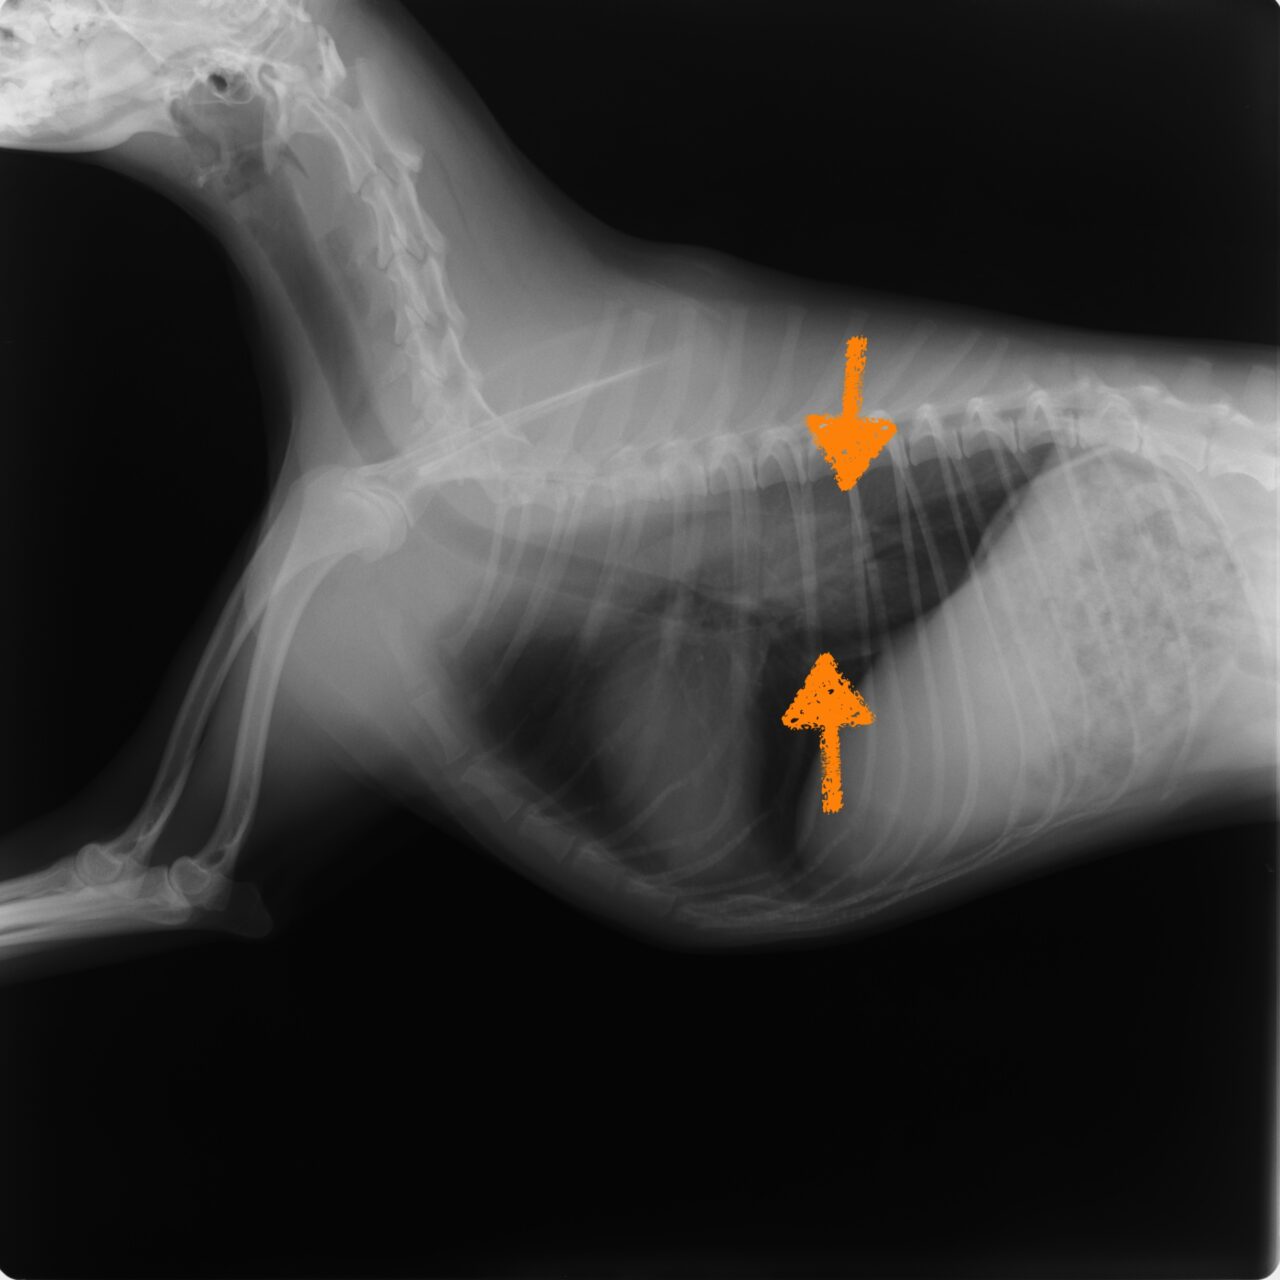

食道内異物

リンゴを小さなお子さんがワンコに与えてしまい、しばらくしてワンコが泡を吹き始めて苦しそうにしている。食道内でリンゴによる異物閉塞を引き起こしたとのこと。かかりつけ医の迅速な評価で、当院に搬送され内視鏡を用いた非侵襲的アプローチによって対応しました。日常生活における誤飲防止も大切です。飼い主さんも平素から予防策を心がけましょう。

- 診断方法:X線および内視鏡検査